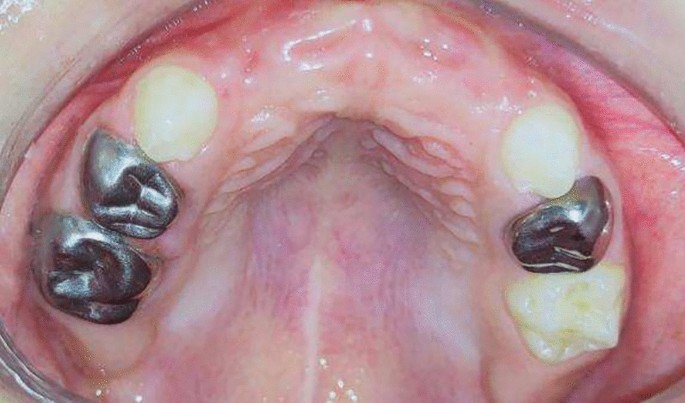

Group II (control group): Twenty preschool children used a modified Nance appliance in their anterior extraction site. (Fig4, 5)

Premature loss of upper ant teeth.

Rehabilitation of extraction site with modified Nance appliance.

Group II:

The first step was done in group (I) was performed, then primary impression was taken for selection appropriate stainless-steel bands on second primary molars. After proper adaptation of the bands, secondary impression was taken and sent them to the dental laboratory for construction of modified Nance appliance.

A modified Nance appliance was constructed by 0.9 mm rigid stainless steel wire welded to each band then extended to the raugae area of hard palate where heat cure acrylic resin poured into it, then part of the acrylic resin extended into alveolar ridge as artificial acrylic teeth would embedded in the acrylic resin. Figure 5